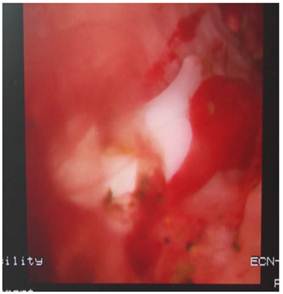

Eight patients, 6 males and 2 females (mean age of 56.3 years; range of 35 to 76 years), who underwent LC and LCBDE, were included in this retrospective, non-randomized trial. The informed consent was obtained from all patients. Postoperative 2-3 months later they went back to out-patient clinic for radiography via T-tube with contrast agent. Consequently, filling defects were found in radiographies in all patients. As a result, all patients were admitted into hospital in order to do fiberoptic choledochoscope. The patient took supine position, with Pethedine intramuscularly injected, then T-tube was removed from sinus. Skin around tube were disinfected with Iodine. Fiberoptic choledochoscope (Olympus, Tokyo, Japan) was inserted into sinus and CBD, and rough CBD inner wall attached with inflammation floc was found. Clips and stones were seen in CBD, which is shown in Fig. 1, and removed with stone-retrieving basket (Olympus, Tokyo, Japan) successfully. Of all patients, in 6 cases there was a single clip in CBD, and 2 clips in other 2 cases. After the procedure was completed, a drainage tube, which was usually removed next day, was dwelled into CBD sinus to drain the fluid in the CBD out of body after no residual stone in CBD was confirmed. The patients were discharged the next day without complications.

Figure 1

Clips and stones in CBD were revealed by fiberoptic choledochoscopy.